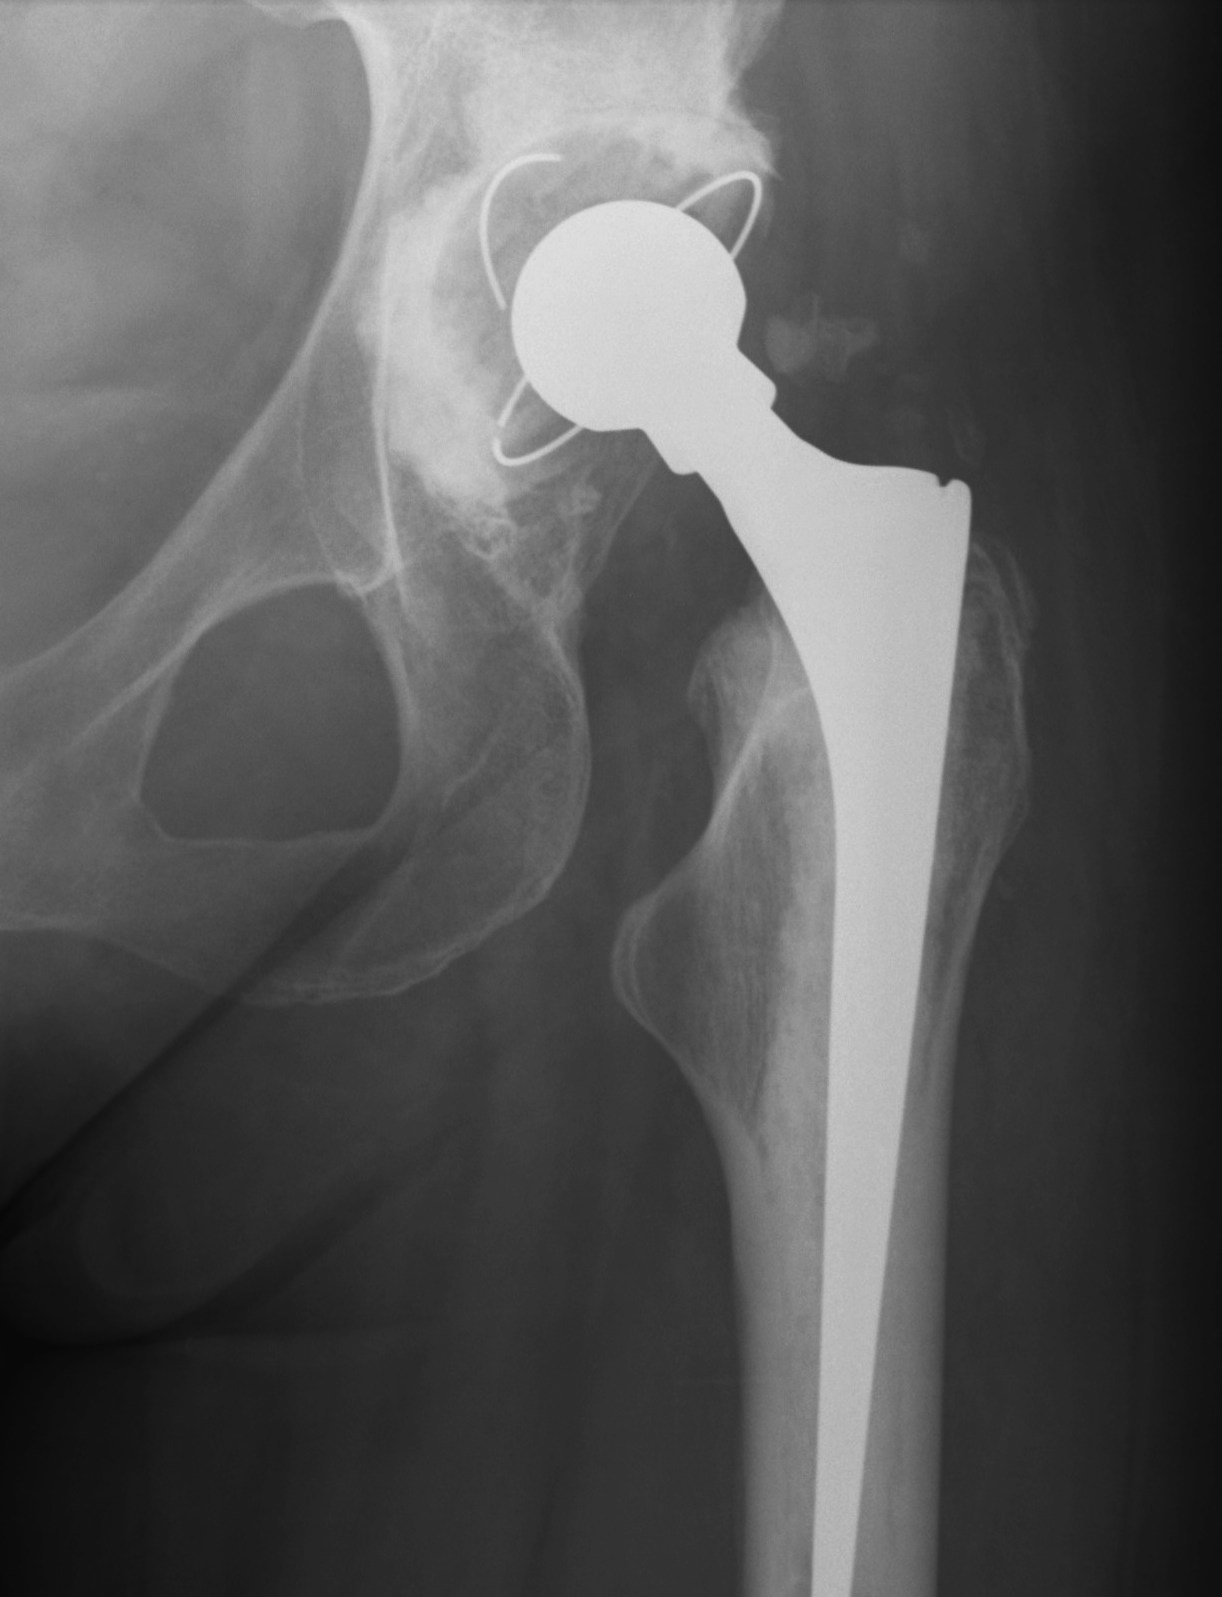

Crowe I

Crowe II

Crowe III

Crowe IV